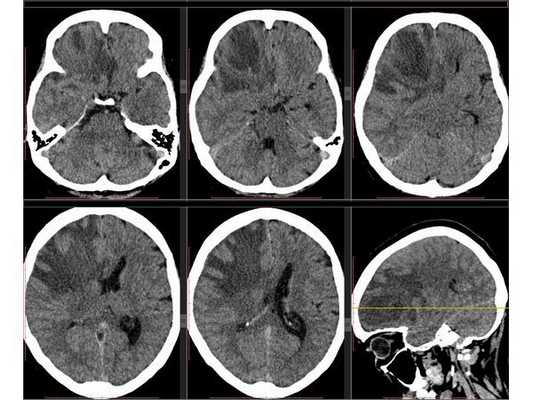

Рентгенография лёгких: без патологии. УЗИ органов брюшной полости: выявлены хронический холецистит, хронический панкреатит, диффузные изменения печени и поджелудочной железы. ЭКГ: в норме. На КТ головного мозга визуализировалось объёмное образование в правой лобной доли. Это вызвало подозрение на абсцесс, но отсутствие уровня жидкости, лихорадки и менингеального синдрома у пациентки в большей степени склонило клиническую мысль в сторону онкологического поражения. В связи с этим пациентку госпитализировали в отделении неврологии. Однако при осмотре онкологом и гинекологом данных, которые бы подтверждали наличие онкологии головного мозга, обнаружено не было. В качестве дообследования проведена КТ головного мозга с контрастным усилением. Она выявила объёмное образование в правой лобной доли с чётко очерченной капсулой. Рядом с образованием располагался отёк, срединные структуры были смещены влево примерно на 5 мм.

3D-реконструкция объёмного образования правой лобной доли головного мозга, выполненная на основании сканов КТ с контрастным усилением